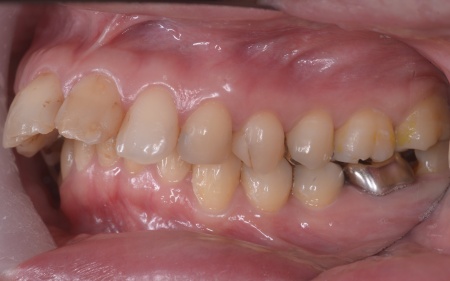

30代女性 出っ歯と開咬に対しアンカースクリューを用いたワイヤー矯正で治療した症例

拝見したところ、上前歯が大きく前に出ている上顎前突であり、上下の前歯が噛み合わずに口を閉じても前歯同士が接触しない「開咬(かいこう)」の状態でした。

患者様の場合、骨格的な上顎前突が噛み合わせを乱している主な原因であることから、矯正治療では前歯を後方へ大きく動かすためのスペースを確保する必要があります。

上顎の奥歯(第1小臼歯)を左右1本ずつ抜き、奥歯にアンカースクリューを埋め込みます。上奥歯をしっかりと固定することで、抜歯で確保したスペースを最大限に活用しながら、前歯を効率よく後方へ牽引することが可能です。

治療の結果、前歯が正しく噛み合うようになり、横顔のバランスも整いました。